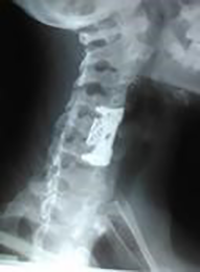

Se indica realizar resonancia magnética, evidenciando la existencia de una lesión ocupante de espacio a nivel de C5-C6, de aspecto subdural. En vista de estos hallazgos, se procede a realizar laminectomía en C5-C6 con abordaje posterior en donde, posterior a incisión de la duramadre, se aprecia la existencia de una lesión quística. Se logra realizar exéresis completa de la misma, ya que no presenta adherencias a la médula espinal. La laminectomía se puede apreciar en la radiografía de la columna cervical postoperatoria (Figura 1).

Figura 1: Radiografía de columna cervical anteroposterior, donde se evidencia laminectomía en C5-C6 con abordaje posterior.

Si bien es cierto que, en los controles médicos posteriores, la paciente demuestra mejoría significativa de los síntomas neurológicos antes descritos, al año de la cirugía se le indica realizar nuevamente una resonancia magnética, en vista de presentar molestias a nivel cervical. En el estudio, se aprecia una pérdida de la lordosis cervical, por lo cual se le realiza fijación de la columna vertebral con corpectomía cervical a nivel de C5, insertándose malla y placa de titanio, logrando la estabilidad de la columna y mejoría de la cervicalgia (Figura 3).

Figura 3: Radiografía lateral de columna cervical, donde se evidencia fijación de la columna, mediante abordaje anterior, con colocación de malla y placa de titanio, por técnica de corpectomía cervical a nivel de C5.